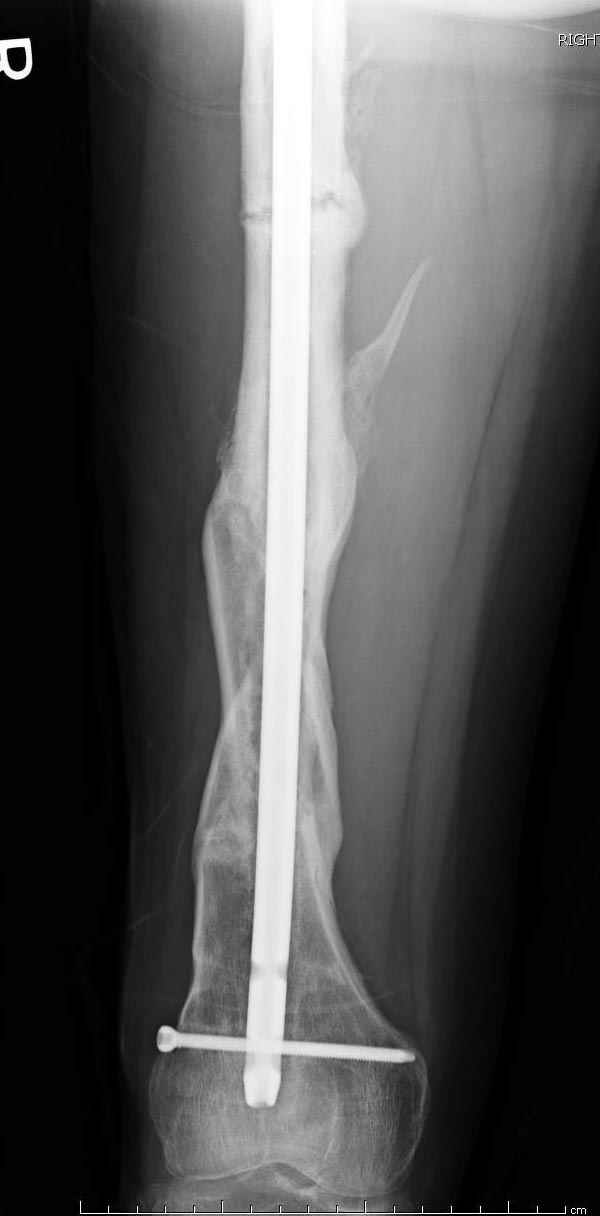

Мы не дождались “Happy End”, у больного IQ в пределах 70%, через 6 месяцев вернулся после небольшой травмы, споткнувшись получил перелом

того же бедра (рис №7).

На следующий день произвели интрамедуллярный остеосинтез: этапы во время операции (рис №8, №9)

и последующих снимках (рис №10, 11, 12, 13) перелом сростается и передвигается с полной нагрузкой.